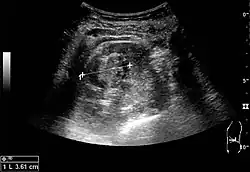

Figure 9. Renal cell carcinoma with both cystic and solid components located in the cortex. Measurement of tumor on the US image is illustrated by '+' and a dashed line.[1]

A solid renal mass appears in the US exam with internal echoes, without the well-defined, smooth walls seen in cysts, often with Doppler signal, and is frequently malignant or has a high malignant potential. The most common malignant renal parenchymal tumor is renal cell carcinoma (RCC), which accounts for 86% of the malignancies in the kidney. RCCs are typically isoechoic and peripherally located in the parenchyma, but can be both hypo- and hyper-echoic and are found centrally in medulla or sinus. The lesions can be multifocal and have cystic elements due to necrosis, calcifications and be multifocal (Figure 8 and Figure 9). RCC is associated with von Hippel–Lindau disease, and with tuberous sclerosis, and US has been recommended as a tool for assessment and follow-up of renal masses in these patients.[1]